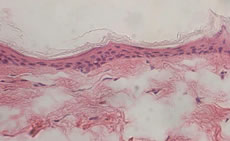

Durch sukzessives Züchten einer Dermis aus Fibroblasten und einer Epidermis mit Stratum Corneum aus Keratinocyten entsteht innerhalb von 5 Wochen ein Ganzhautmodell, das alle wesentlichen Schichten der Haut enthält (6) (Abb. 2). Die immunohistologische Analyse zeigt, dass sowohl die epidermalen Differenzierungsmarker als auch die Proteine der Basalmembran und der dermalen Matrix ähnlich exprimiert werden (Tab. 1).

Abb. 2: Histologischer Vergleich zwischen Ganzhautmodell (oben) und normaler menschlicher Haut (unten)